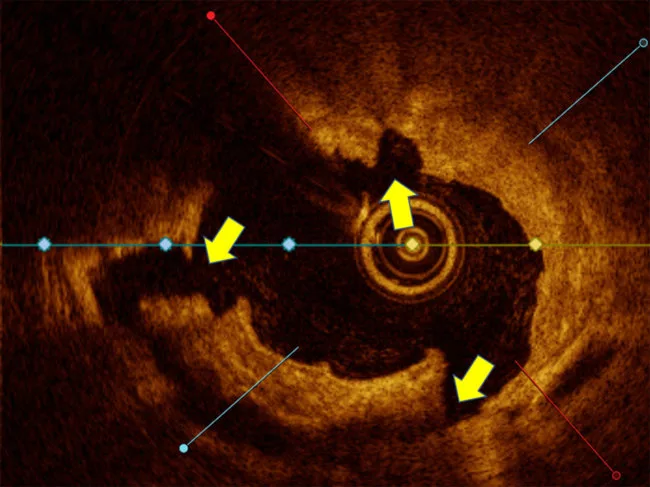

intravascular-image-optical-coherence-tomography-showing-large-cracks-in-plaque.jpg

Safety of Elixir’s Lithix Hertz contact lithotripsy catheter validated

Elixir Medical Corp. revealed that data from the Pinnacle I study has validated the safety and effectiveness of its Lithix Hertz contact intravascular lithotripsy system to treat moderate to severe calcified coronary artery lesions by percutaneous transluminal coronary angioplasty. Read More